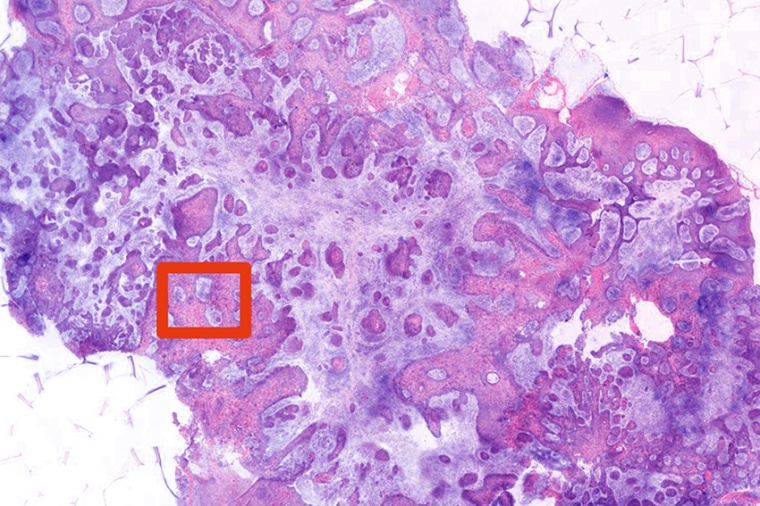

Giacomelli is developing a novel imaging system, contained on a portable cart, to shorten this process to two minutes. This would enable a surgeon to immediately determine whether the lesion is cancerous and, if so, to “treat the patient during the same visit instead of stretching it out over the next month and multiple visits.” The system –using two-photon fluorescence microscopy (TPFM) – demonstrated remarkable accuracy in a pilot study. When tested on 15 biopsies of known nonmelanoma skin cancer, the technology was able to detect basal cell carcinoma with perfect accuracy – 100 percent sensitivity and specificity – and squamous cell carcinoma with high accuracy – 89 percent sensitivity and 100 percent specificity.

The advantage of using TPFM is that it not only generates high-resolution images but it also uses near-infrared light that penetrates deeper through tissue, making it “advantageous for rapid imaging of fresh, irregularly shaped biopsies with minimal preparation,” the researchers note. Giacomelli is now working closely with Sherrif Ibrahim, an associate professor of dermatology at the University’s Medical Center, on a larger, 200-patient follow up study, using biopsy samples taken at random at Ibrahim’s Rochester Dermatological Surgery in nearby Victor, New York.